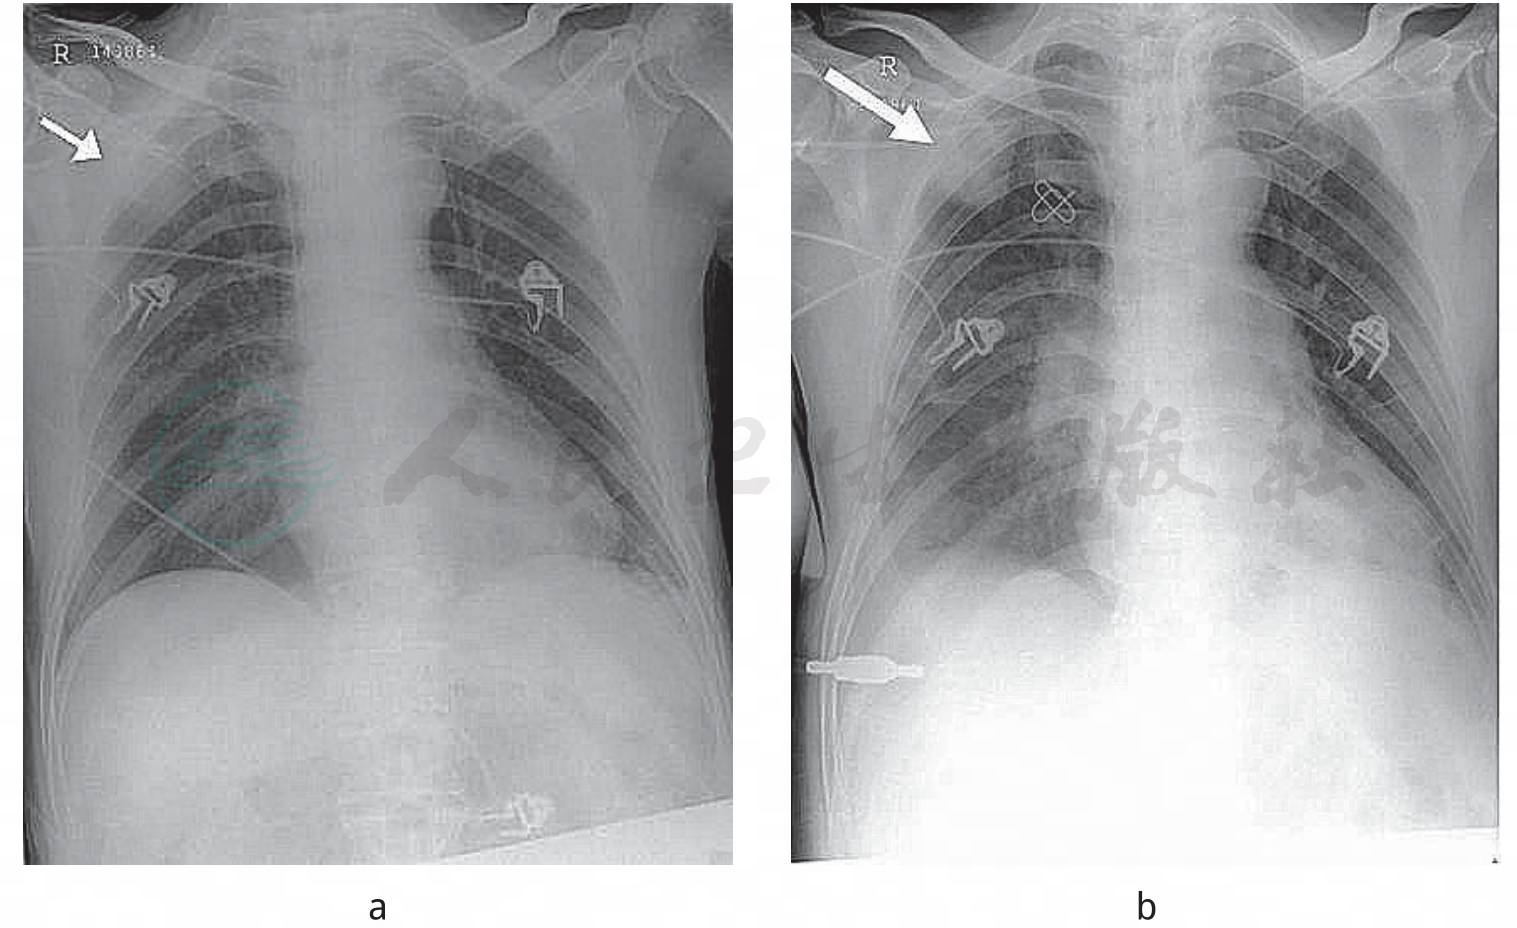

啰音。心率106次/分,心律不齐,第一心音强弱不等。腹部未见异常。四肢肌张力低下,肌力0级,病理反射未引出。化验WBC 27.1×109/L,N 93.9%,Hb 105g/L,PLT 221×109/L,BUN 26.9mmol/L,CRE 161μmol/L,K+ 4.43mmol/L,Na+ 156mmol/L,Cl-121mmol/L,ALT 49IU/L,AST 108IU/L,ALB 24.8g/L。入院后立即行气道分泌物细菌及真菌涂片和培养,有铜绿假单胞菌,未查到真菌。床边胸片示双肺纹理增强,右上肺斑片状阴影;3日后阴影更明显(图1)。

图1 胸片示右上肺斑片阴影(箭头所示)

a.入院当日;b.入院第3天